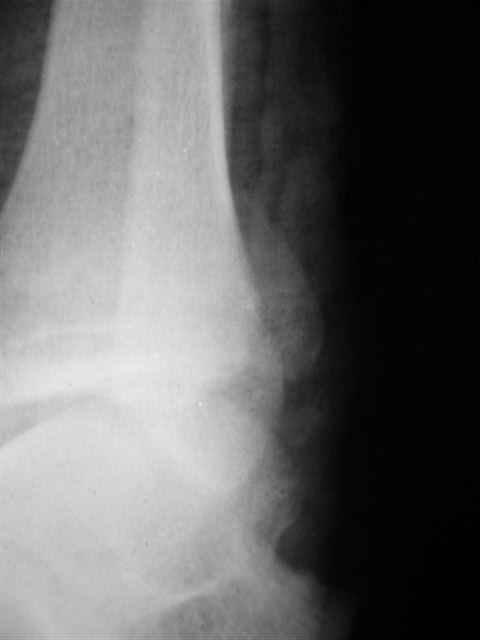

> Если Вас не затруднит, пришлите, пожалуйста, рентгенограммы. Я

> интересуюсь тактикой лечения повреждений голеностопного сустава.

> Хочется посмотреть, как лечат коллеги.

Ничего сверхъестественного, но если есть интерес, то в понедельник пересниму Рг-граммы и отправлю.

Я предупреждал, что ничего сверхъестественного. Каюсь, что одна из спиц прошла несколько дальше, чем нужно было, но главное - перелом стабилизирован и больной работает суставом в полном объёме, несмотря на представленную раннее травму коленного сустава.